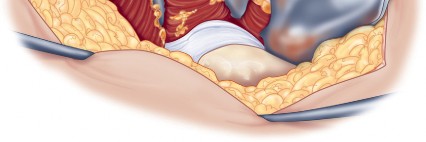

Component Preparation and Implantation

With the acetabulum fully exposed, the labrum is excised, and osteophytes are removed to identify the true floor of the acetabulum (cotyloid fossa). Sequential reaming is performed until punctate bleeding from subchondral bone is achieved. The acetabular component is then impacted into place, targeting approximately 40 to 45 degrees of inclination and 15 to 20 degrees of anteversion.

Following acetabular fixation, the femur is elevated and externally rotated for preparation. A box chisel is used to open the femoral canal laterally, ensuring neutral alignment to avoid varus malpositioning of the stem. Sequential broaching is performed until rotational stability is achieved. Trial components are placed, and the hip is reduced to assess leg length, offset, and stability through a full range of motion. Once satisfied, the definitive femoral stem and head are implanted.

Meticulous Closure

Closure is a critical phase of the direct lateral approach. The anterior flap of the gluteus medius and vastus lateralis must be securely repaired to the posterior cuff of the tendon left on the greater trochanter. Heavy non-absorbable sutures or strong absorbable sutures (e.g., #2 or #5) are utilized. Some surgeons prefer transosseous tunnels through the greater trochanter to ensure a robust repair. Failure to achieve a secure closure can lead to abductor avulsion, resulting in a persistent Trendelenburg gait and lateral hip pain. The fascia lata is closed meticulously to prevent fascial herniation, followed by standard subcutaneous and skin closure.